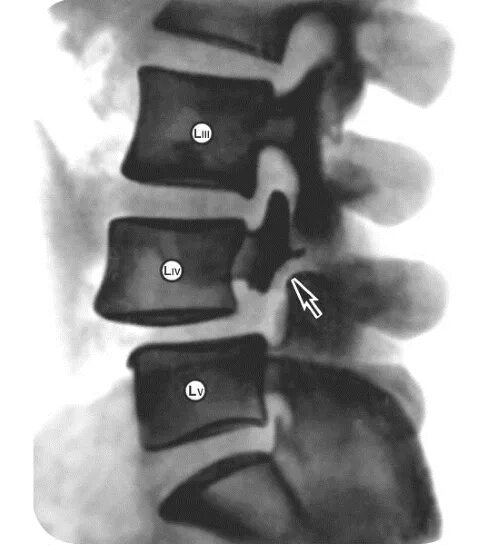

L 5 3